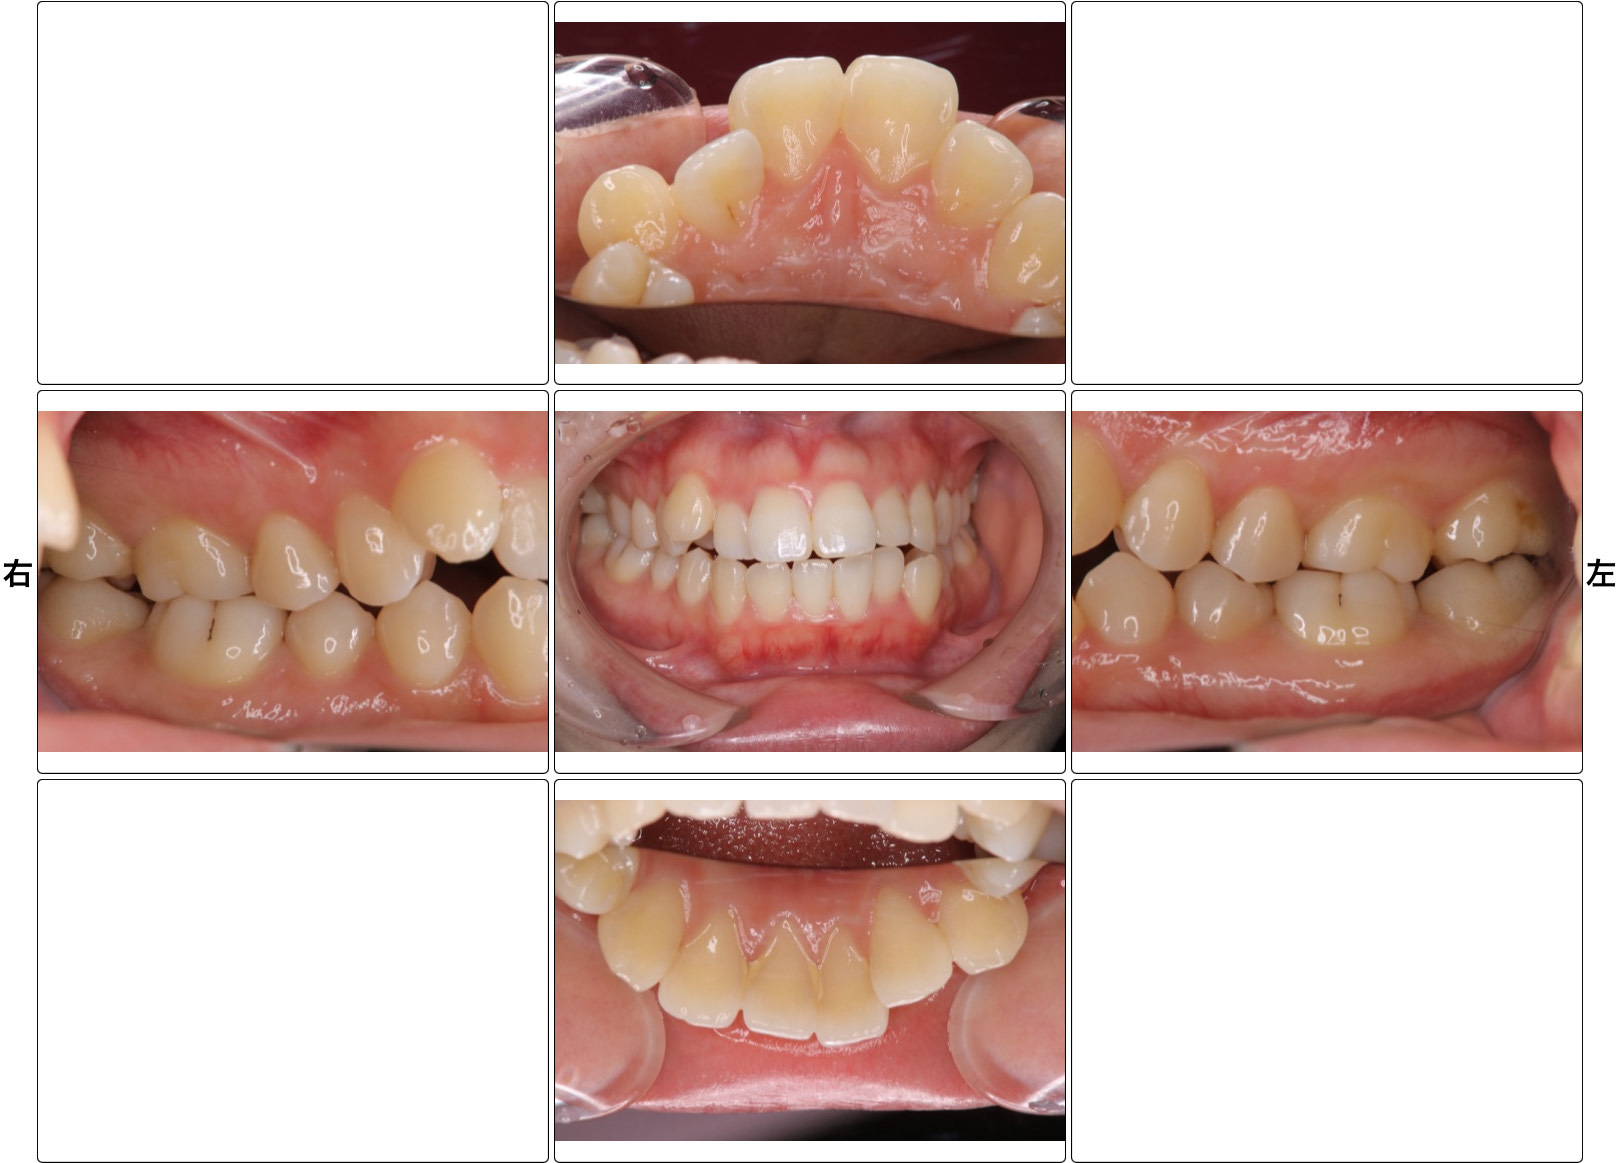

矯正治療の症例

- 治療の説明

- ブラケット矯正を行いました。

上下顎前突、叢生、オープンバイトの患者様です。上下左右4番目の歯を抜歯し、マルチブラケットを使用して歯並びを治しました。 - リスク

- 痛みを伴う可能性がある。口内炎が出来る可能性がある。歯根吸収の可能性がある。ブラックトライアングルができる可能性がある。

- 費用

- 85万(税込935,000円)〜、+調整料